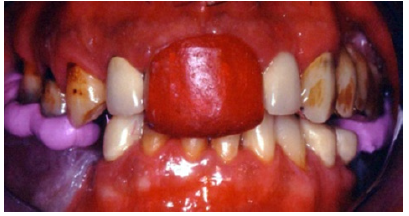

Preparations for veneers, final result

In order to optimize final aesthetics the 5 mandibular anteriors were prepared for all ceramic restorations. Four all ceramic veneers (E-max Ivoclar Co, Liechtenstein) and an all ceramic crown (#42) completed the final restorations. A final occlusal splint was also fabricated chairside (prior to the final cementation of ceramic veneers) for the protection of final restoration and control of TMJ function (Figure 19,20). Minimal occlusal modifications of the splint were necessary after final cementation of mandibular anteriors. The final radiographic examination was kept as a record for future re-examinations (Figure 21). Finally, the patient was enrolled to a 3 months recall program. In each recall and maintenance visit, the periodontal tissues, the abutments and the stomatognathic system were thoroughly examined, preventive regimens were applied and patient compliance was assessed. Two years later, the excellent periodontal condition and performance of the restoration was registrated (Figure 22-24). The patient complied with proper oral hygiene, reduced smoking and adopted a regular use of the occlusal splint. Strict recall and maintenance visits were necessary for long term success of this full mouth rehabilitation. The patient stopped smoking immediately after 6 months and changed nutritional habits in order to eliminate secondary caries.

Figure 20: Final restorations after cementation of the all ceramic veneers.